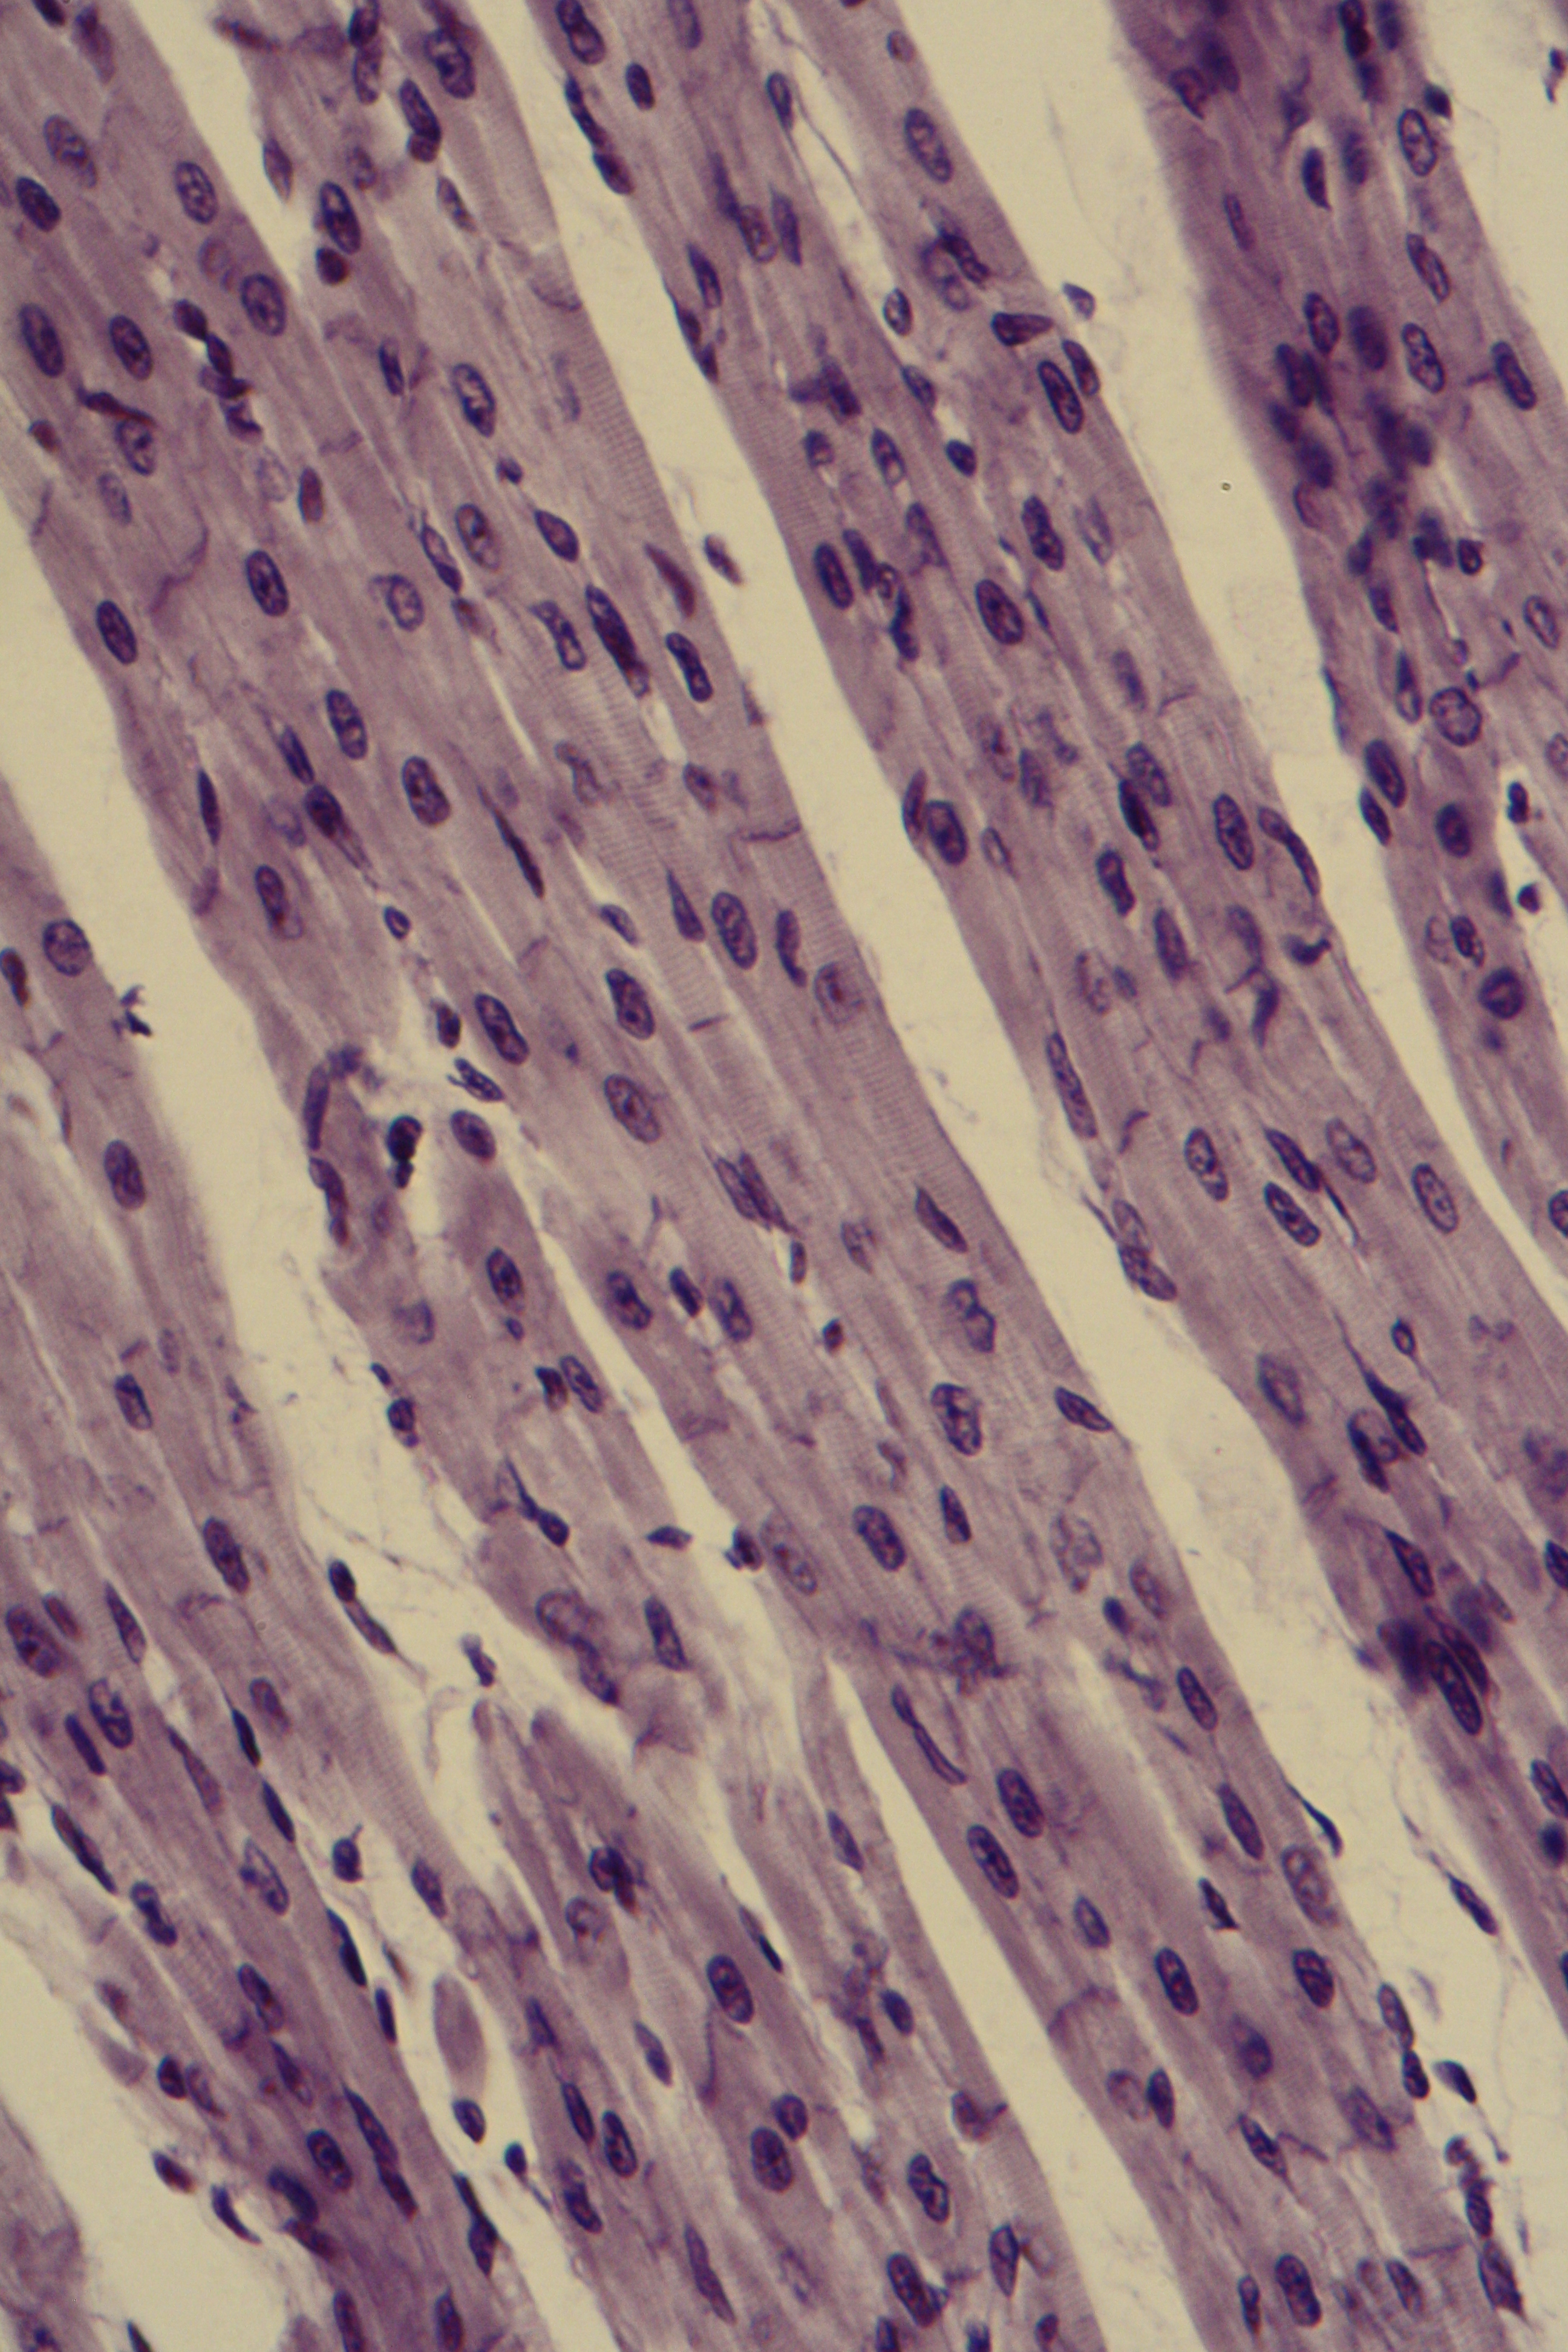

The next two show cardiac cells with intercalated disks.